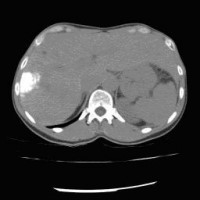

Computertomographische Darstellung eines hepatozellulären Karzinoms (Pfeil)

(Bild 1 von 5)